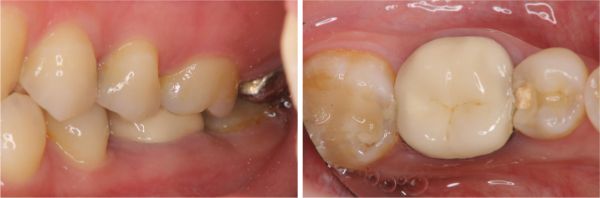

治療前,左下第一大臼齒根尖病變

根尖病變

手術後牙齦仍腫脹

拔牙後待傷口癒合